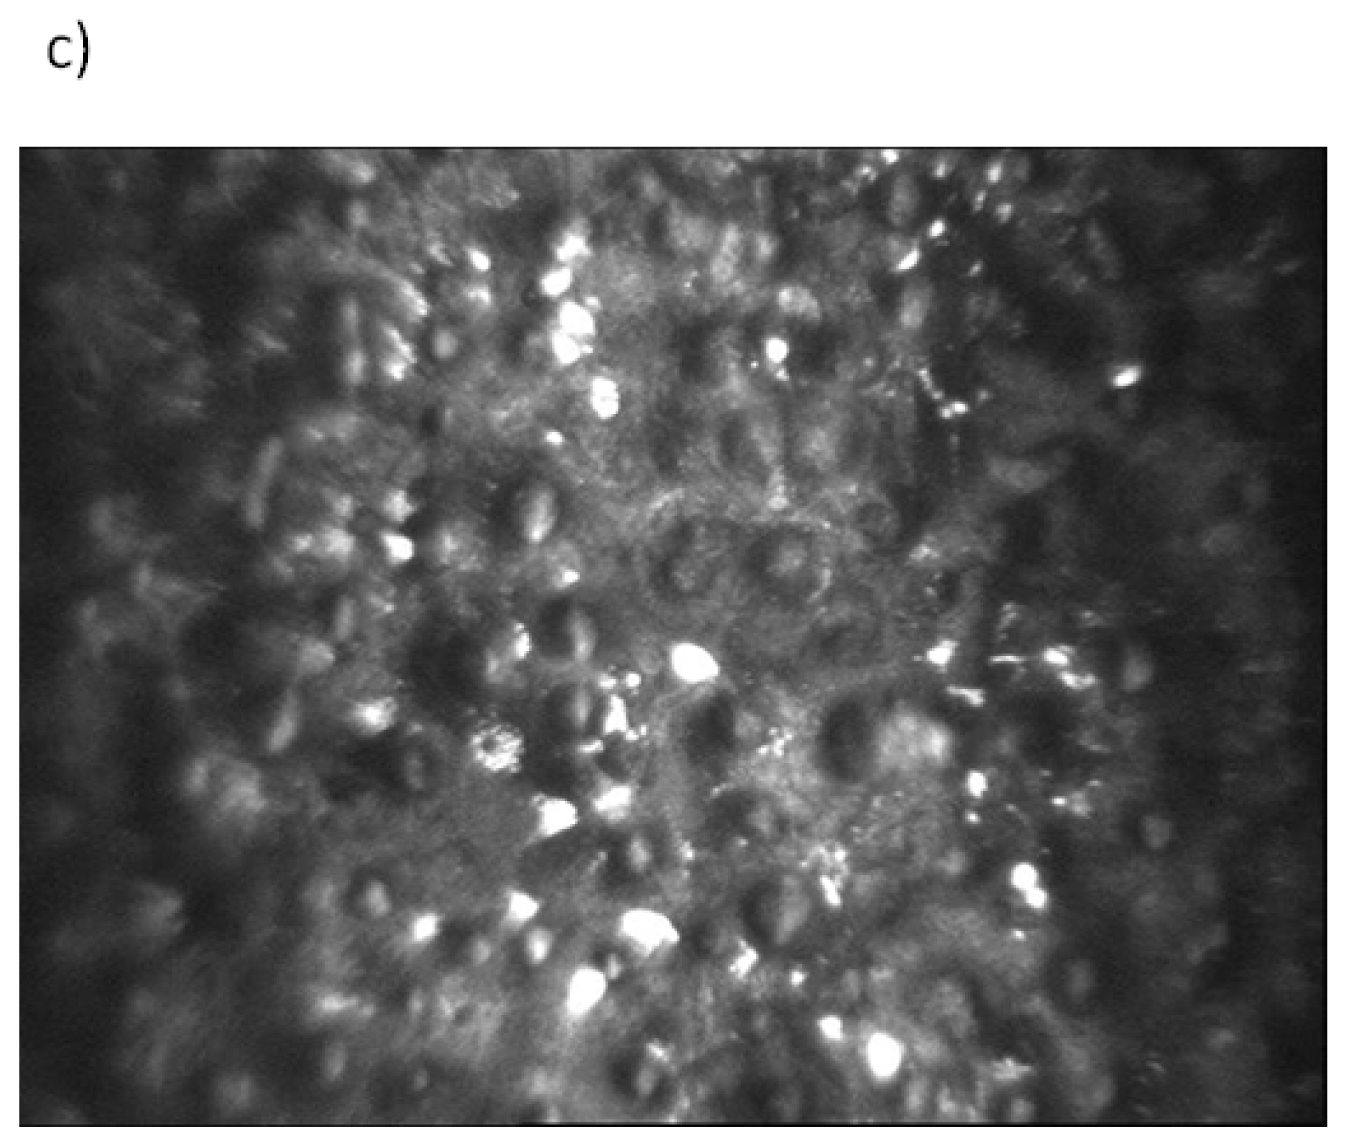

Specular microscopy imaging of the corneal endothelium (CE). (a Keratoconus Specular Microscopy Web qualitative and quantitative structural changes were seen in endothelial cells of keratoconus eyes by using. Qualitative and quantitative structural changes were seen in endothelial cells of keratoconus eyes by using. Web specular microscopy of donor corneas is a standard practice in the. Web the review focuses on the principles of specular microscopy, limitations of endothelial imaging, and its interpretation. Keratoconus Specular Microscopy.

Fig l. Normal human corneal epithelium showing flattened polygonal Keratoconus Specular Microscopy Web specular microscopy is a noninvasive photographic technique that allows you to visualize and analyze the corneal endothelium. Web specular microscopy of donor corneas is a standard practice in the. To investigate the effect of the severity of keratoconus on the corneal endothelium using specular microscopy. Web the review focuses on the principles of specular microscopy, limitations of endothelial imaging,. Keratoconus Specular Microscopy.